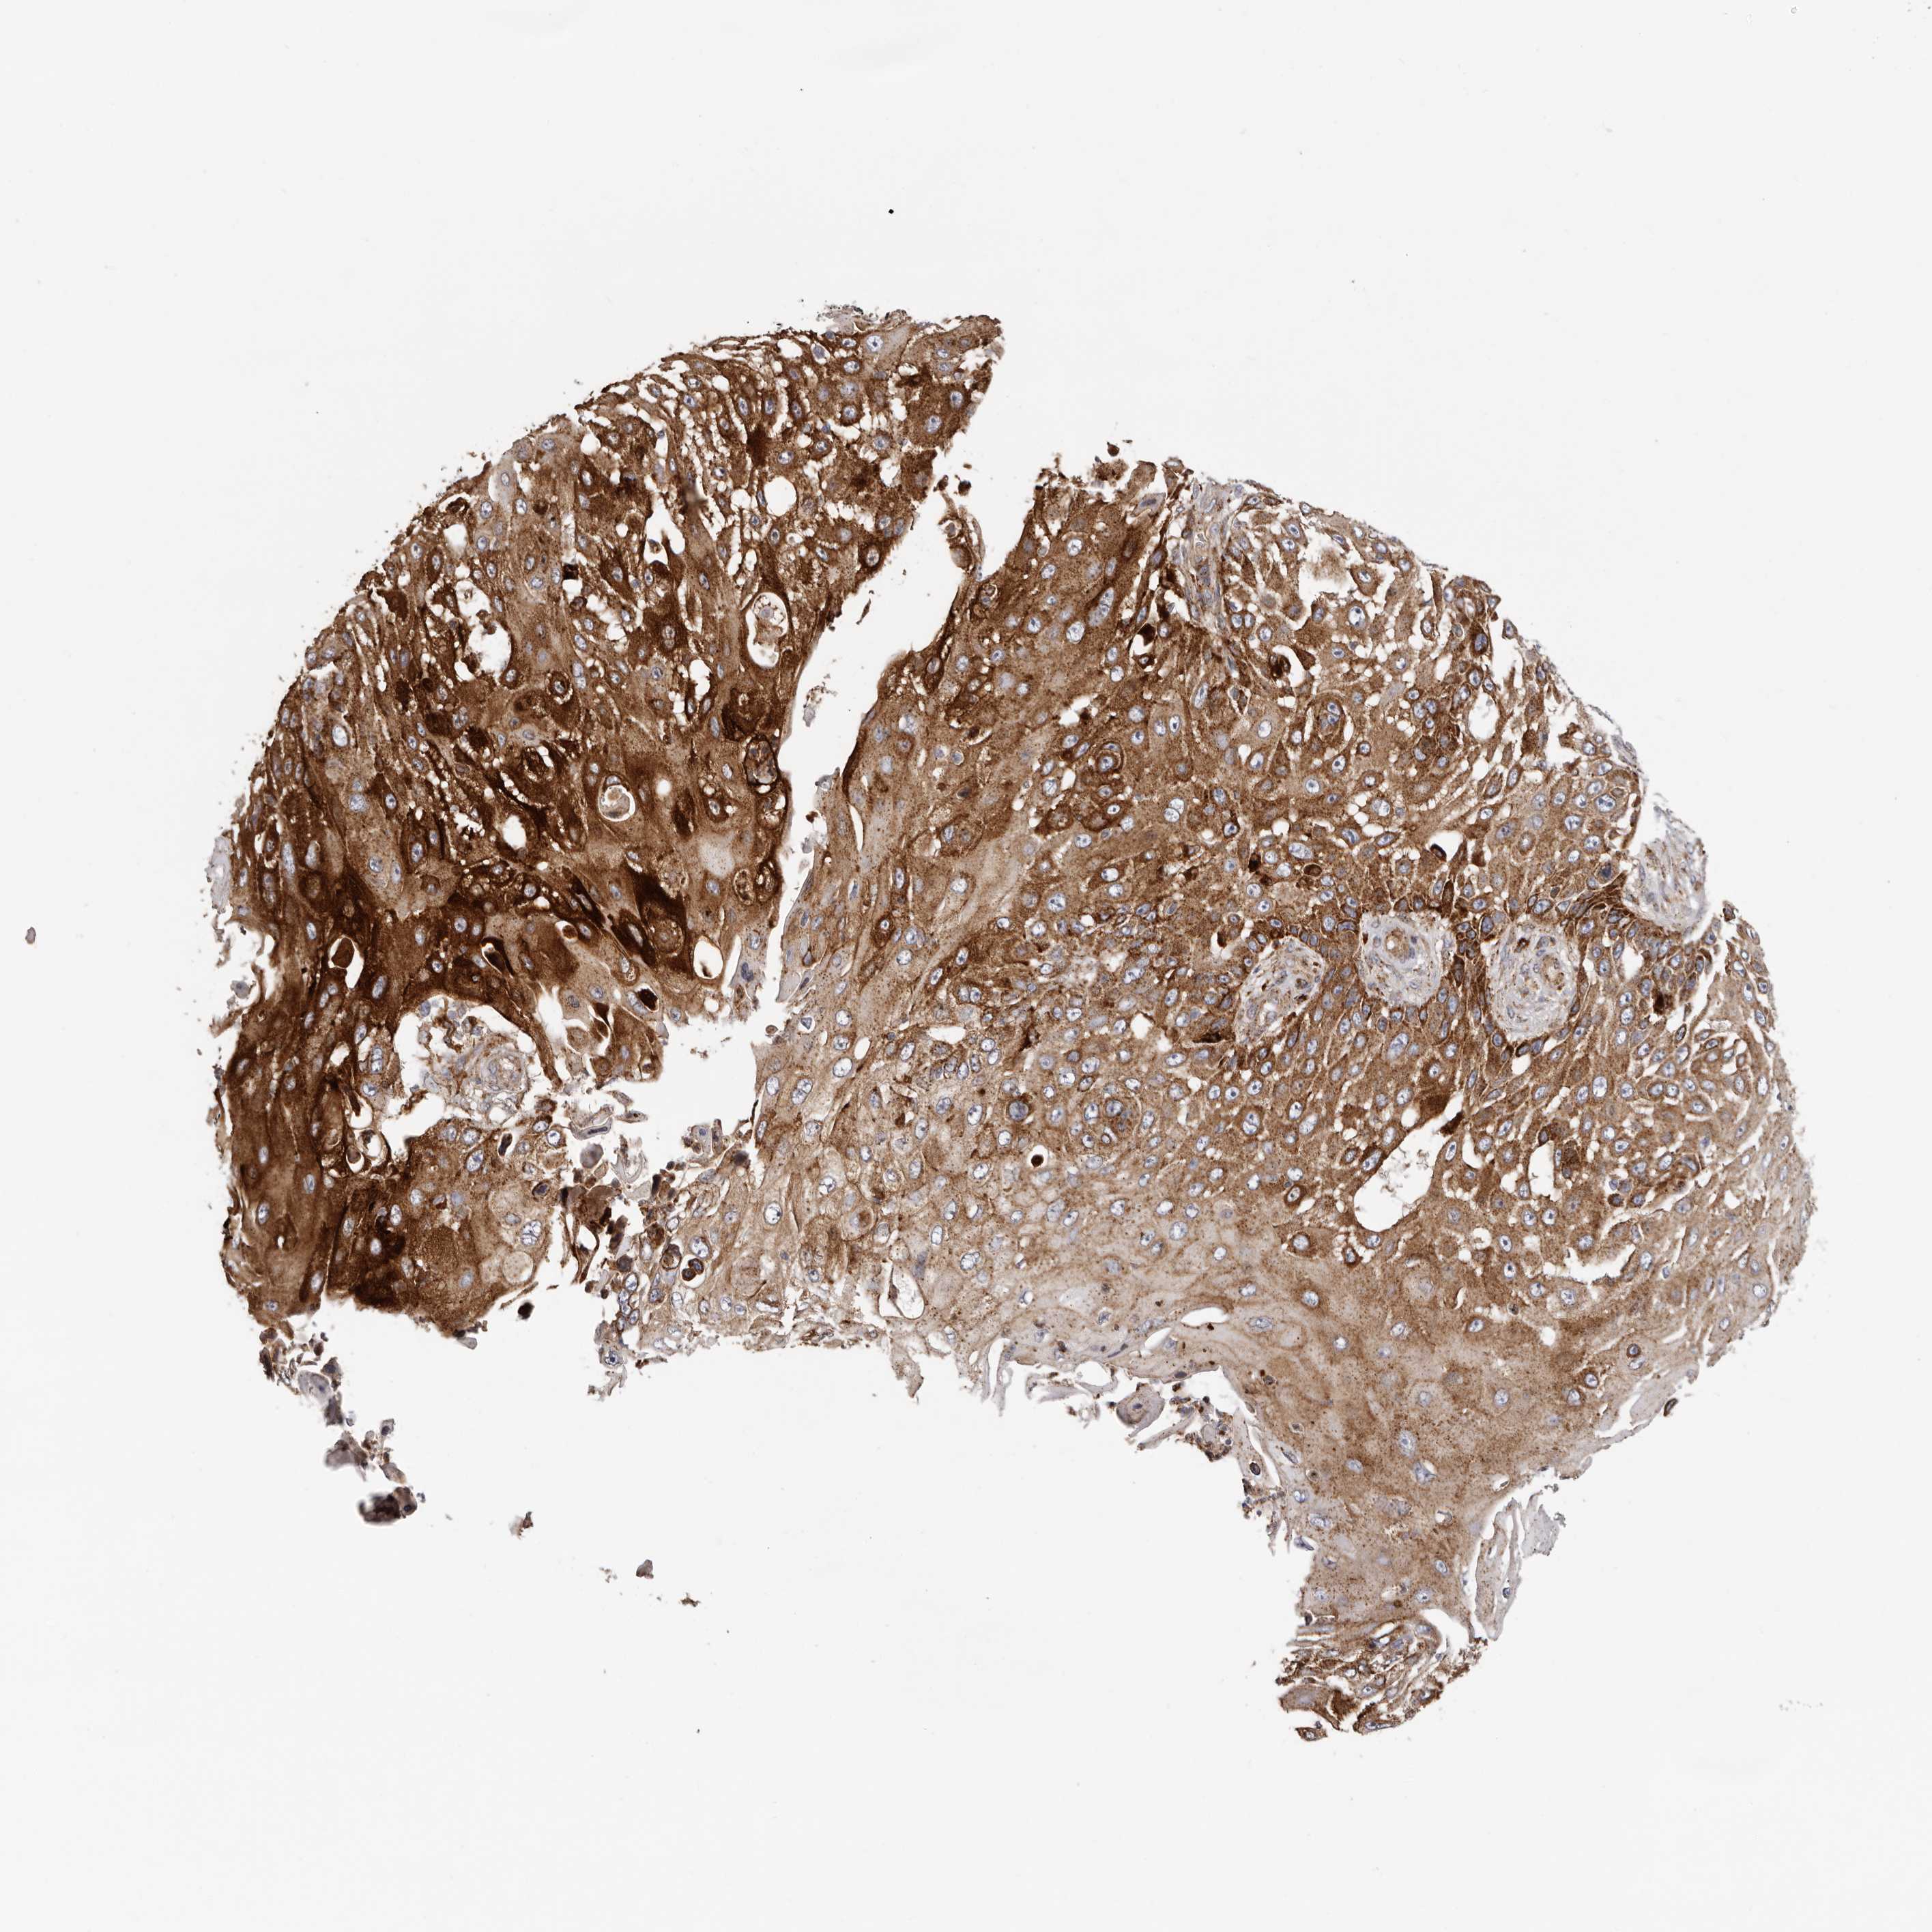

SKIN CANCER - Protein expressioni

A mouse-over function shows sample information and annotation data. Click on an image to view it in a full screen mode. Samples can be filtered based on level of antibody staining by selecting one or several of the following categories: high, medium, low and not detected. The assay and annotation is described here.

Antibody stainingi

Antibody staining in the annotated cell types in the current human tissue is reported as not detected, low, medium, or high, based on conventional immunohistochemistry profiling in selected tissues. This score is based on the combination of the staining intensity and fraction of stained cells.

Each image is clickable and will lead to virtual microscopy that enables deeper exploration of all samples and also displays staining intensity scores, fraction scores and subcellular localization as well as patient and tissue information for each sample.

Antibody HPA028747

Staining

High

Strong

>75%

Cytoplasmic/membranous

Squamous cell carcinoma, metastatic, NOS